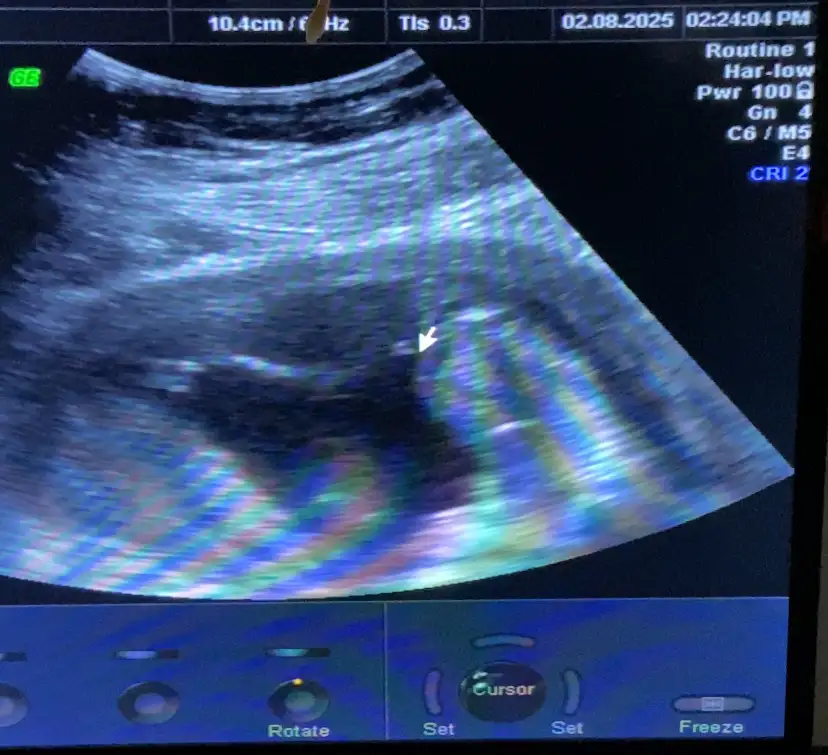

Senin ortada belli malesef canım ama Kordon olabilir mi ki senin kaçıncı çocukKızlar bu da benim bebeğimin usg si 14. Hafta bacak arası görüntüsü. Doktor yüzde yüz erkek dedi ama ben hala bi sonraki kontrolü bekliyorum çünkü kız hissediyorum. Ceylin sana da belki fikir olur diye attım

İkinci çocuk, bir kızım var. Kordon olduğunu sanmıyorum çünkü kan akışına da bakıyorlar ya kan akışı olanlar kordon oluyor. Doktorum ona da baktı 10 dakika falan sadece cinsiyete baktı. Demek ben kendimi ikinci kıza çok hazırlamışımSenin ortada belli malesef canım ama Kordon olabilir mi ki senin kaçıncı çocuk

Yaaa ama şuna bak 14de pipiler görünüyor bende yok ama hala şüpheli konuşuyor bu doktor kafayı yiyecemmKızlar herkese iyi haftasonları. Size 14+2 den pipili bi foti bırakmak istedik ok un hemen solundaki, yavrucum baş aşağı duruyordu fıngır fıngır